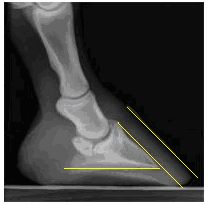

Over the past 22 years the horses that have been referred to me have presented angle differentials of P3 anywhere from: forward rotation resulting in sole penetration, (on left) to reverse rotation which would manifest itself as prolapsed and collapsed heels. (on right)

I have witnessed the palmer surface of P3 on a level landing, sound, shod foot to be at many different angles, the wall on the other hand will be trying to, stay parallel with P3 in the dorsal section, thus the heel length will vary in order to try and land level.

It is obvious that a solid steel shoe should hit the ground as level as possible, to avoid a second reaction of jarring. A well shod horse with a level footfall and correct brake-over is far less likely to have caudal problems than a foot that either lands heel or toe first.

The barefoot horse that is fed correctly and in the right conditions will choose, when sound and balanced, to land heel first and rotate its weight and propulsion through the foot ending in a natural brake-over that it creates itself.

As the foot is landing heel first the production and consistency of the frog and heel tissue is paramount to the soundness of the animal. The heel wall will not be as long as a shod foot as it is not trying to avoid a heel landing.